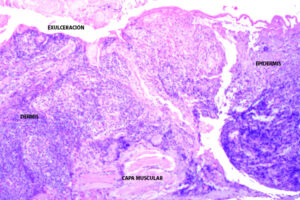

La leishmaniasis cutánea en el párpado comparte las características histológicas generales de la forma cutánea, pero su localización periocular (cercana a estructuras sensibles) la hace particularmente importante. La histopatología de